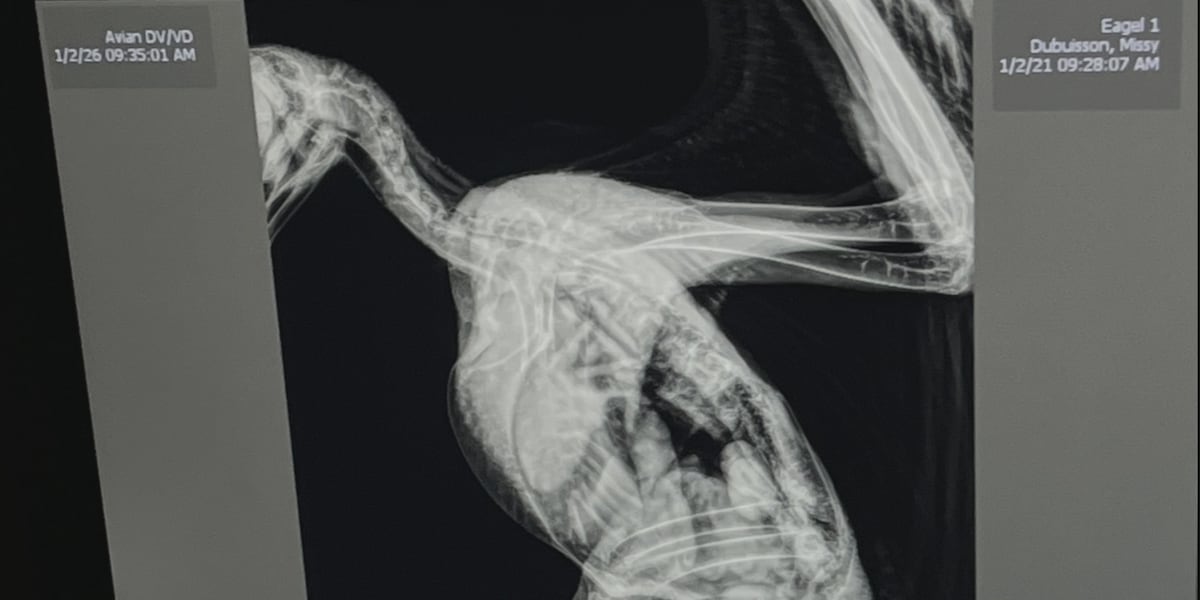

After X-rays, veterinarians determined Kringle had likely suffered a previous injury that forced him to rely on roadkill for food. The lack of proper nutrition caused his bones to weaken over time.

“I’m thinking it got rear ended by some car because it was eating roadkill. It had a fractured back and spine at about the lumbar region. After the days and weeks they’ve been doing rehab on it, it just didn’t improve and it was not going to make it any better,” said Dr. James Askew, Wild at Heart veterinarian.

Kringle’s spine was broken in three places and had deteriorated almost completely.